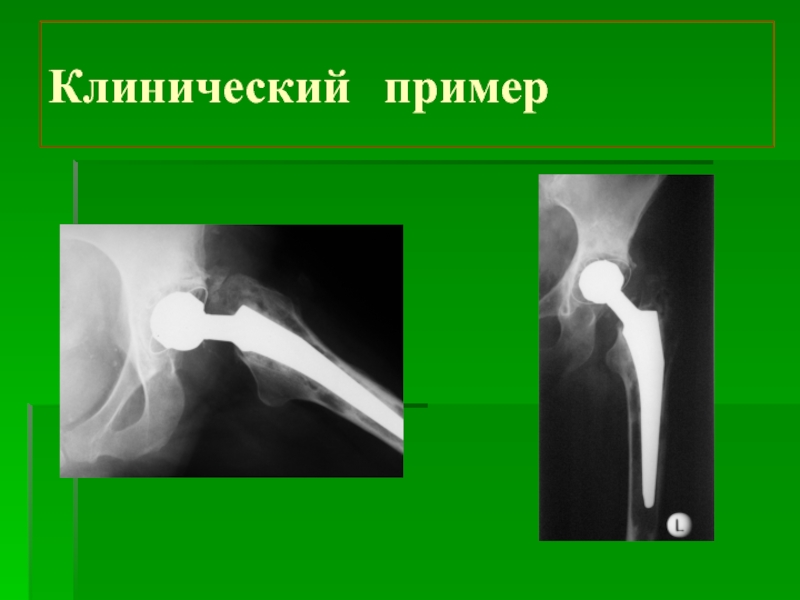

Слайд 17Клинический пример

Клинический пример